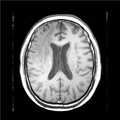

도 2는 본 발명의 일실시예에 따라 획득된 제1영상의 예시도면이다.

2 is an exemplary diagram of a first image acquired in accordance with an embodiment of the present invention.

고해상도 영상인 제1영상(100)과 저해상도 영상인 제2영상(200)을 획득한다(S100). 고해상도 영상(제1영상(100))은, 도 2에서와 같이, 많은 픽셀로 구성되어 공간적으로 선명하여 혈관 내 위치를 정확한 파악이 용이한 영상을 의미한다. 저해상도 영상(제2영상(200))은, 도 3에서와 같이, 고해상도 영상에 비해 비교적 해상도가 낮아(즉, 각 프레임당 영상을 구성하는 픽셀의 수가 적어) 선명도가 떨어지는 영상을 의미한다. 컴퓨터는 영상촬영장비에 제1영상(100) 및 제2영상(200) 촬영을 직접 요청하여 획득할 수 있고, 영상촬영장비에 의해 이미 촬영된 제1 및 제2영상(200)을 컴퓨터 내부 또는 외부서버에 저장해두고 분석을 수행할 때 불러올 수 있다.The